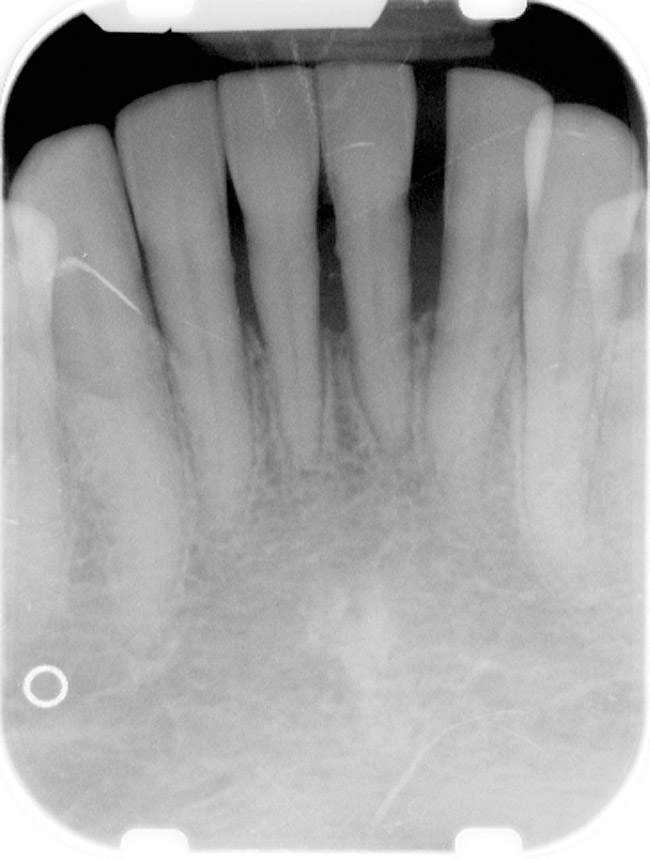

Figure 4  Radiograph of oral bisphosphonate user.

Figure 4

Under the sextant approach, one quadrant is treated and the patient is left to heal for 2 months before proceeding to any additional quadrants. While the patient heals, a 10-day course of antibiotics and 2 months of twice-daily chlorhexidine rinsing may be prescribed. Figure 4 shows a patient who was taking oral bisphosphonates for 3 years and was treated with the sextant approach. As seen in the radiograph, the patient has one molar in the lower right quadrant. This tooth was extracted and the patient was given 2 months to heal (Figure 5 and Figure 6). The patient was placed on antibiotics and chlorhexidine rinse. After 2 months, no signs of BRONJ were observed, and the anterior teeth were scheduled for extraction. They were extracted as atraumatically as possible, and the site was sutured (Figure 7 and Figure 8).The patient then was given another 2 months to heal, following the previous protocol. After 2 months of healing, no BRONJ was observed (Figure 9).